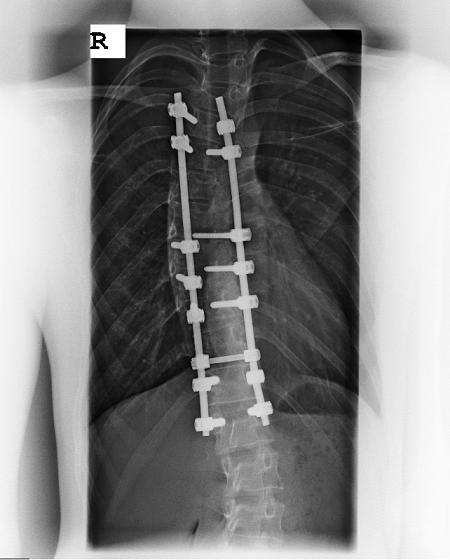

Meine Narbe sieht jetzt nur aus wie ein lange Kratzer sonst seh ich auch wieder aus wie jeder andere. Ich habe ein Röntgenbild angehängt, Wirbel wurden nur an der BWS versteift.

- Wirbelsäule2.JPG (27.6 KiB) 5951 mal betrachtet